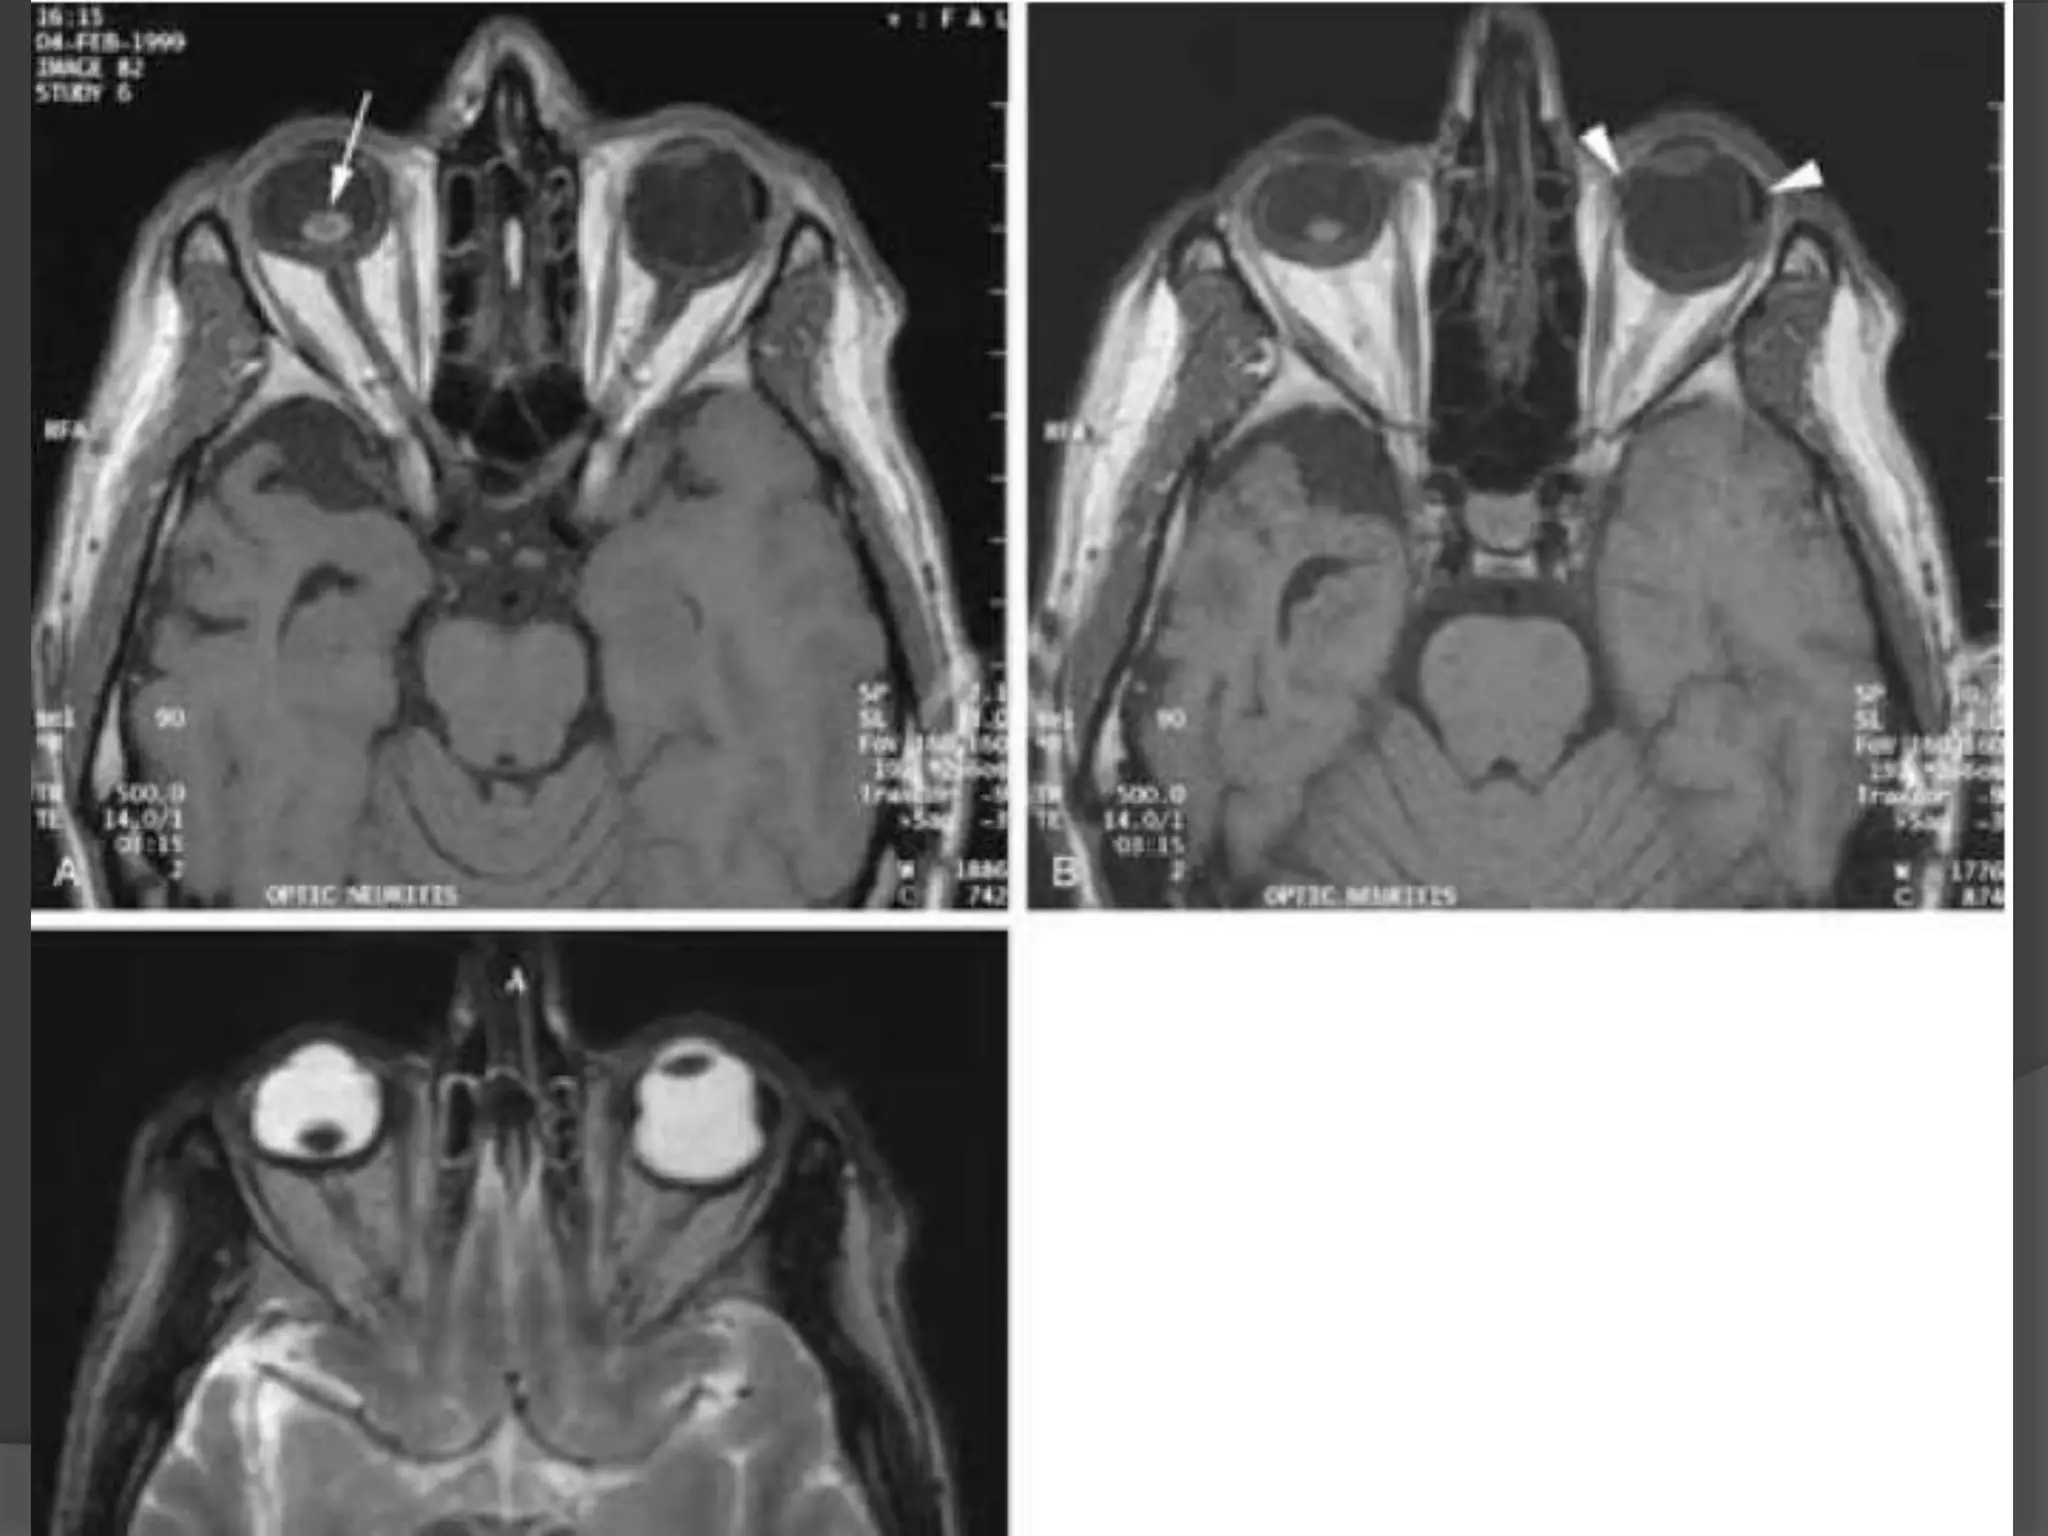

Imaging : MRI is the modality of choice with hyper intense signal of

T2WI due to fluid and edema. Fat Sat contrast enhanced T1WI will show

areas of demyelination. CT relatively insensitive.

Straightening and thickening

of right optic nerve.

Optic Neuritis. CE Fat Sat T1W axial

(B) MR images demonstrate subtle enlargement and enhancement of the left

optic nerve (curved arrow).

T 2 WI (C) demonstrates corresponding increased signal intensity (straight

arrow).

Acute inflammation ofoptic nerve , commonly associated with multiple sclerosis. Edema and inflammatory cells infiltrate the nerve resulting in uniform swelling and focal demyelination. Imaging : MRI is the modality of choice with hyper intense signal of T2WI due to fluid and edema. Fat Sat contrast enhanced T1WI will show areas of demyelination. CT relatively insensitive. Straightening and thickening of right optic nerve.

Optic Neuritis. CEFat Sat T1W axial (B) MR images demonstrate subtle enlargement and enhancement of the left optic nerve (curved arrow). T 2 WI (C) demonstrates corresponding increased signal intensity (straight arrow).